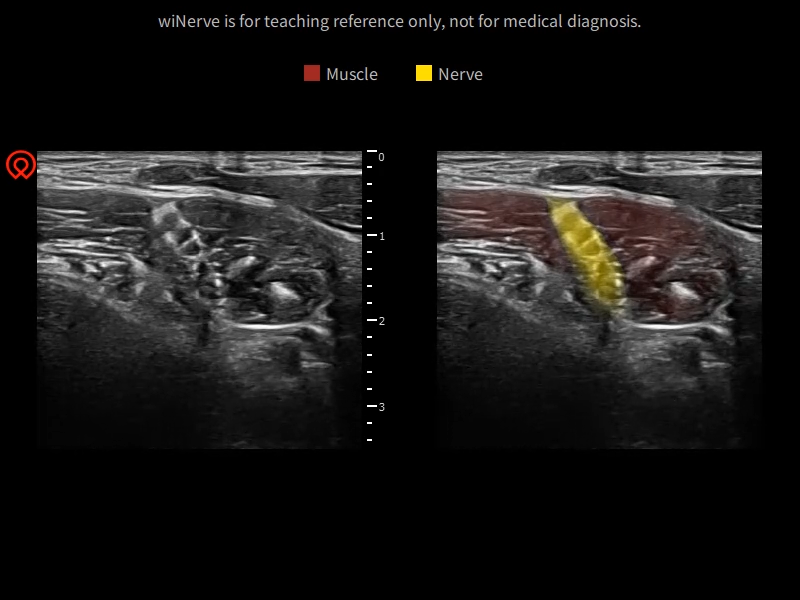

wiNerve - Интеллектуальное распознавание нервов AI

Распознавание в реальном времени

Облачное решение

Поддержка нескольких нервов

Онлайн-руководство